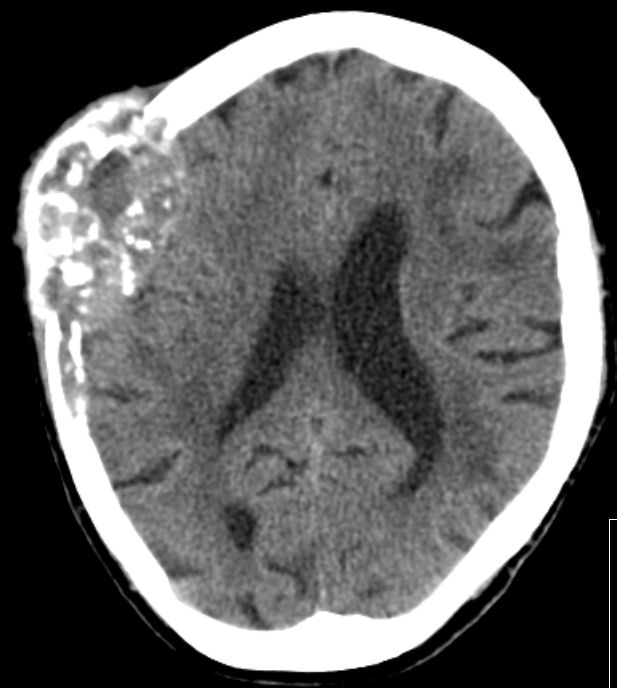

| Schädel | 86-jährige Frau mit primär ossär metastasiertem Adenokarzinom des linken Oberlappens.

Monate nach Diagnose klagte die Patientin über eine schmerzlose Schwellung des Kopfes rechts. Das Nativ-CT zeigt eine Metastase des Schädelknochens.![]() |

Nach KM-Gabe deutliche Kontraststeigerung.![]() |

Im Knochenfenster deutlich größere Zerstörung sichtbar.![]() |